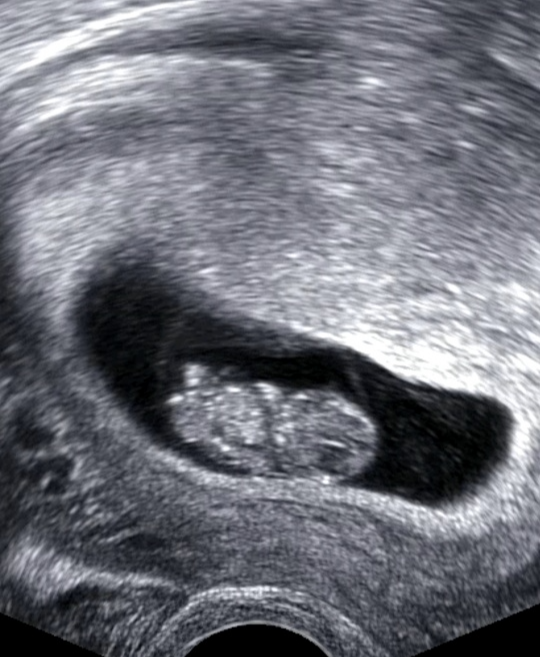

처음 임신을 알게된건 임신 극초기때였습니다. 계속 기다리던 아기라 계속 테스트기를 하기도 했고 느낌이 이상해 산부인과를 방문했지만 초음파로는 보이지 않았고 피검사로 임신을 했다는 사실을 알게됐습니다. 5주가 됐을무렵 아기집이 생기고 난황이 보였습니다.